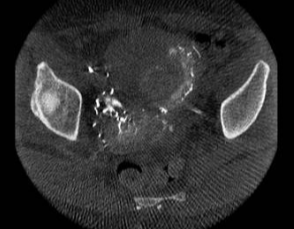

所有年龄超过 40 岁的患者, 卵巢受损 14%-43% 研究中闭经发生率(15%)与单纯UAE报告相似,可能与患者年龄(≥45岁)及卵巢储备自然下降有关。 ![]() 50岁,长期因子宫肌瘤导致月经出血过多,痛经和贫血。 子宫肌瘤栓塞术前,显示双侧子宫动脉发育不全,子宫肌瘤双侧卵巢动脉。 经皮股动脉穿刺双侧卵巢动脉栓塞,先500μm-700μm emboSphere 微球 术后4周,和6月的中短期随访,月经正常,子宫容积减少,贫血纠正,无卵巢功能衰竭。但看起来非灌注容积较少。 术后9月,由于子宫肌瘤持续存在,患者自己希望绝经,行全子宫和双侧卵巢切除术 术后病理,子宫内可见栓塞微粒伴有坏死,卵巢内也见栓塞微粒,但卵巢功能未受损。